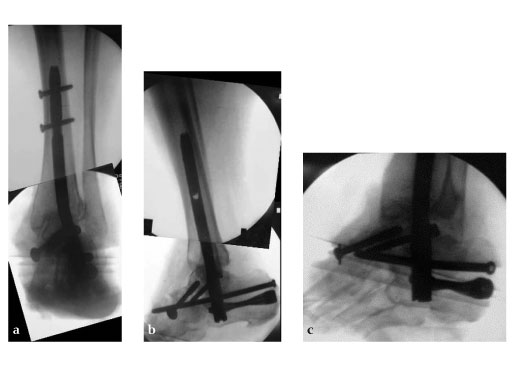

42-year-old, female with severe insulin-dependent diabetes mellitus (IDDM); Charcot foot, wheel chair since 1 year.

Case provided by Hermann Bail, Berlin, DE